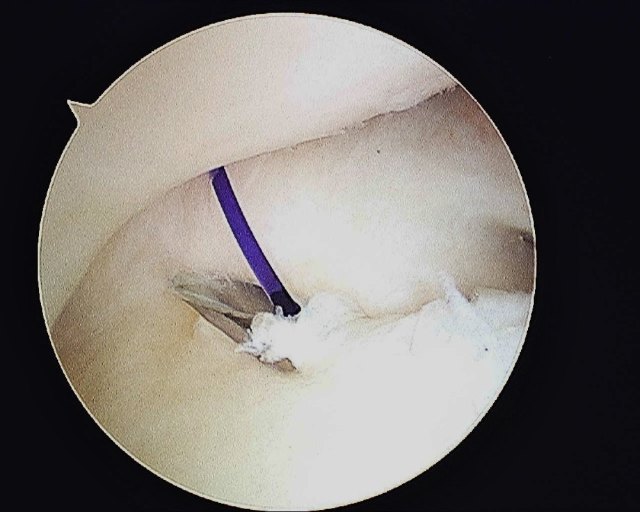

- The tear is repaired with an outside in technique with PDS 3/0 suture. The Smith & Nephew’s TFCC Mender device is used to pass the sutures through the torn TFCC. The sutures are tied outside the capsule while the ECU tendon is being protected by an assistant.

- TFCC Tear – Palmer Type IB